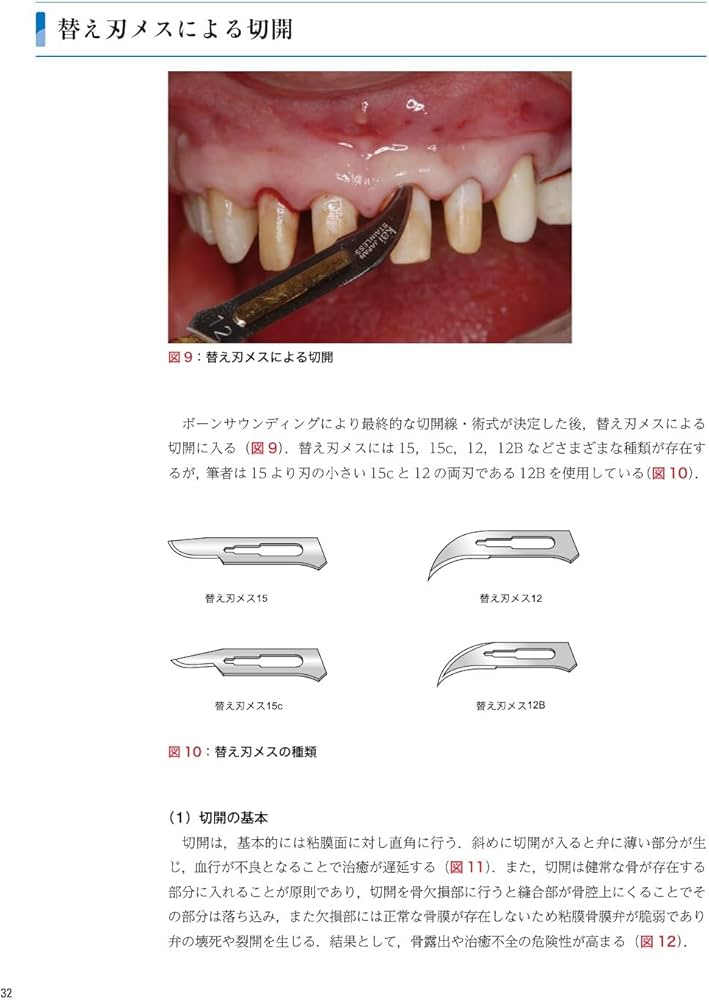

ゼロから見直す歯周外科治療 | 松延 允資 |本 | 通販 | Amazon。ゼロから見直す歯周外科治療/医歯薬出版株式会社。ゼロから見直す歯周外科治療 | 松延 允資 |本 | 通販 | Amazon。天王町、星川の歯医者・歯科で歯周病治療なら横浜アリス歯科・矯正歯科。「ゼロから見直す歯周外科治療」松延 允資定価: ¥ 9000#松延允資 #松延_允資 #本 #自然/医療・薬学・健康